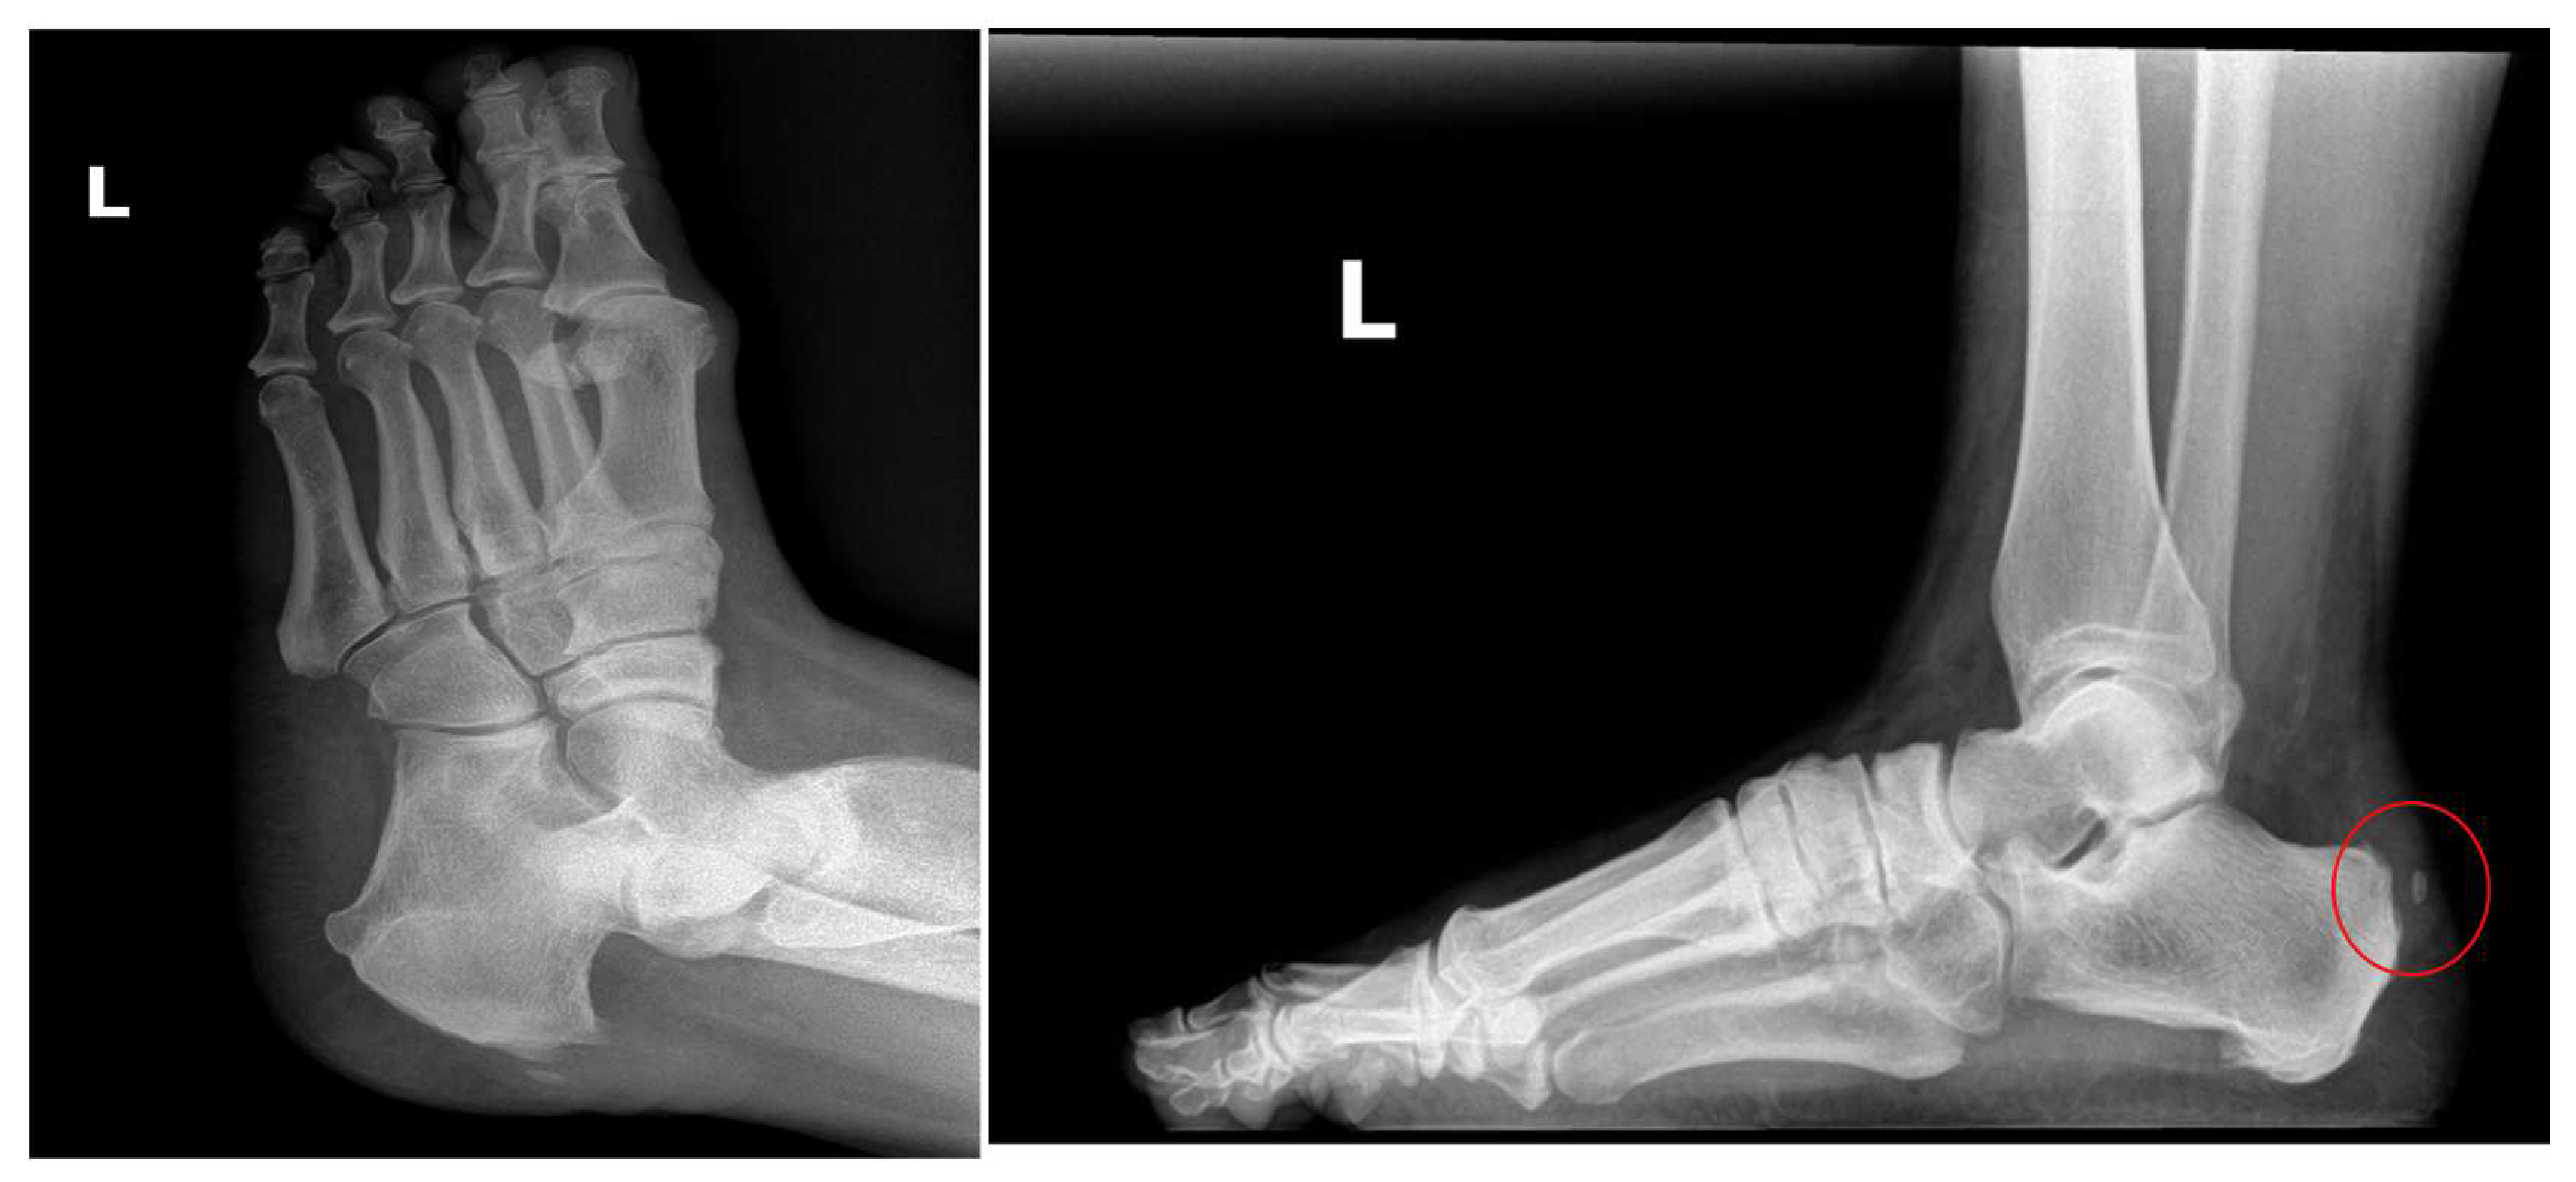

The patient in this study is a 54-year-old female with slow-onset chronic Achilles tendinosis, enthesopathy at the insertion, and retrocalcaneal exostosis. She has been suffering from her condition for three years, which has been progressively worsening. She has failed several standard care treatment modalities, including rest and two procedures. She presented with a retrocalcaneal exostosis of the right leg, severe pain, and declining surgical intervention (Figure 1). Previously, the patient underwent two procedures performed by previous surgeons: one successful inferior calcaneal exostectomy and one minimally successful retro calcaneal resection of the contra-lateral foot (Figure 2). Her work requires her to be on her feet 75% of the time, further aggravating the disorder and causing sharp burning pain. Exacerbating factors include ambulating and standing. To avoid surgery and loss of productive time at work, she sought treatment from Dr. Robert Parker at his clinic, Parker Foot and Ankle, in Houston, Texas. There, she was offered an alternative conservative Wharton’s Jelly structural connective tissue to supplement the structural defects in conjunction with EPAT and class IV laser therapy to promote her body’s own repair processes. This study aims to report pain alleviation secondary to supplementing damaged tendon tissue with Wharton’s jelly and priming the local tendon with EPAT and lasers.

Figure 1. 3/21/2023.

Figure 2. 3/21/2023.

Figure 4. The arrow points to the retrocalcaneal exostosis, and the needle dispensing Wharton’s jelly into the peritendon is circled.

Figure 5. The arrow points to the retrocalcaneal exostosis, and the needle dispensing Wharton’s jelly into the tendon insertion is circled.